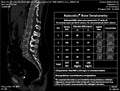

Image:RadnosticsSlicerResults.png|Radnostics(R) Osteoporosis Detection Beta2 integrated into 3D Slicer

Spine Segmentation & Osteoporosis Detection In CT Imaging Studies

Radnostics Osteoporosis Detection is a solution for early detection of osteoporosis in CT scans performed for other clinical indications

• We measure osteoporosis biomarkers and detect patients at risk